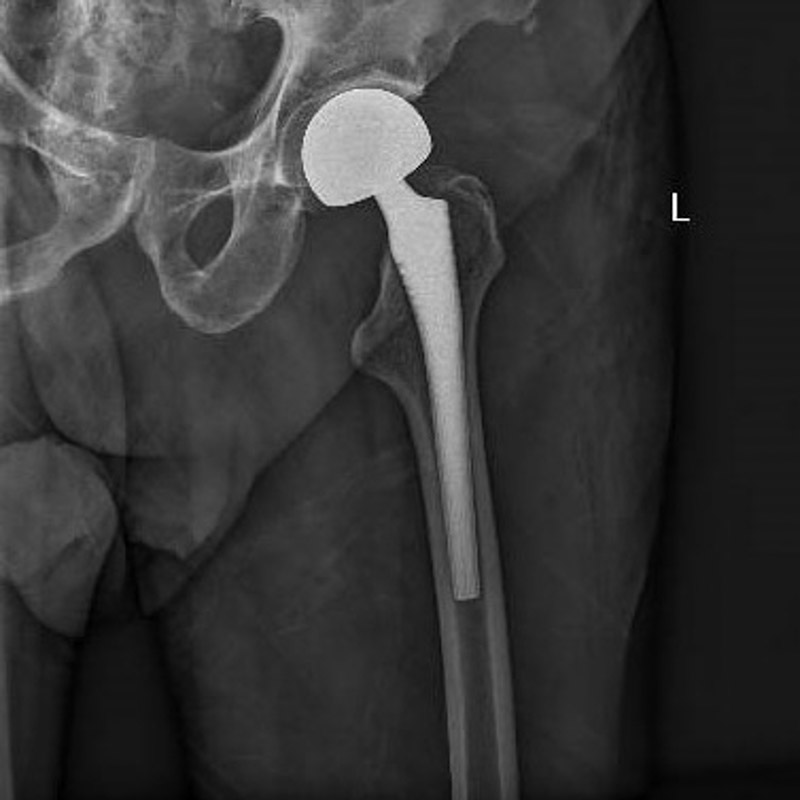

經(jīng)過周密的術(shù)前準(zhǔn)備,6月30日,在麻醉科團(tuán)隊(duì)成功實(shí)施腰椎管內(nèi)麻醉后,創(chuàng)傷骨科團(tuán)隊(duì)為患者進(jìn)行左側(cè)人工股骨頭置換術(shù),手術(shù)過程順利。術(shù)后羅老伯恢復(fù)良好,圍術(shù)期內(nèi)無心肌缺血癥狀發(fā)作,監(jiān)測(cè)心電圖無動(dòng)態(tài)改變。